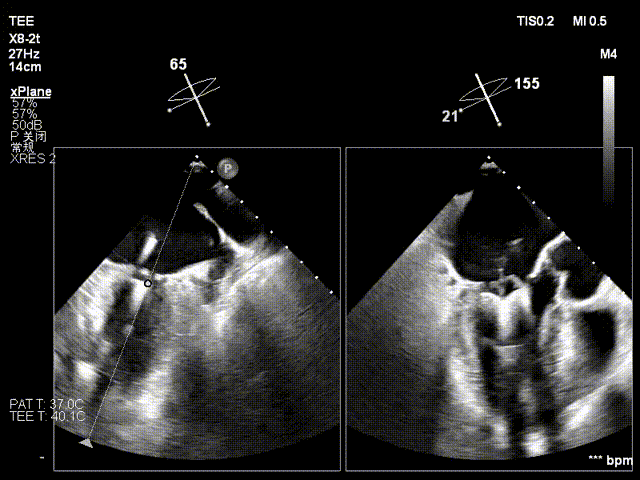

术前心超提示:

退行性二尖瓣反流(DMR),A2-A3脱垂伴连枷样运动(脱垂范围:17mm,连枷间距:7mm),P3脱垂,反流主要位于2-3区,MR重度4+(VC:6*17 mm),A3:18mm,P3:9mm,A2:24mm,P2:14mm,AP:32mm,二尖瓣口面积MVA约 5.6cm²,左房、左室明显扩大。

术中操作(关键步骤超声)

在全麻下,于心尖入路完成ValveClamp®装置植入。术中多学科团队密切配合,超声全程实时指导操作。最终,于2偏3区成功植入一枚Ⅲf夹子,一次夹合完成。前叶夹合量12mm,后叶夹合量10mm,反流降至1+,导管操作时间30分钟。术后平均跨瓣压差3mmHg。